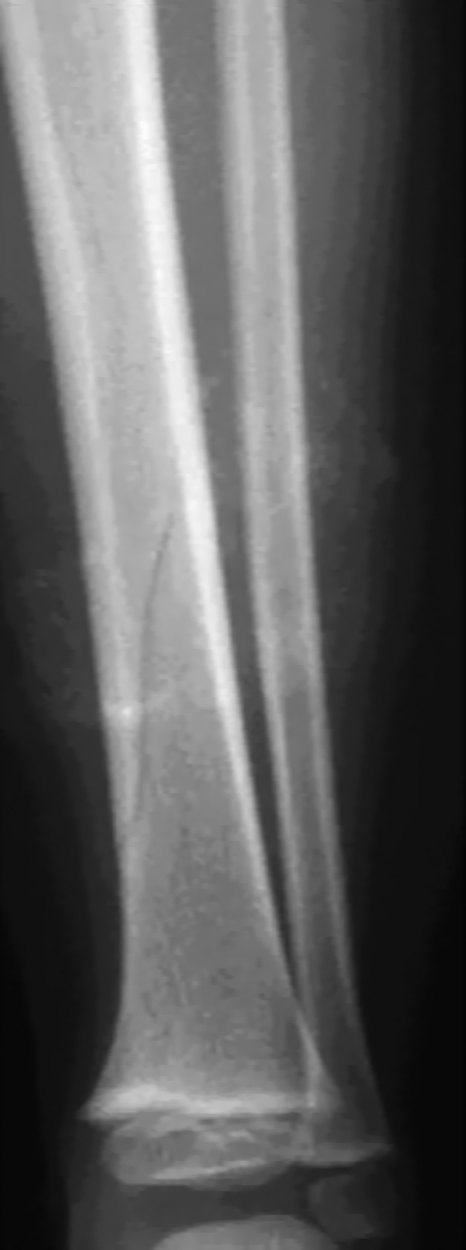

Quel est votre diagnostic ?

Il s'agit de l'aspect radiologique d'une fracture sous-périostée chez l'enfant. Si certaines fractures sont proches de celles rencontrées chez l'adulte, d'autres sont en revanche spécifiques à l'enfant : fractures en motte de beurre, fractures en bois vert, déformation plastique, fractures sous-périostées, décollements épiphysaires. L'os de l'enfant est moins résistant que celui de l'adulte mais il n'y a pas de fracture sans traumatisme, donc pas de fracture avant l'âge de la marche. Le bilan radiographique comprend des clichés avec incidences de face et de profil, englobant les articulations sus- et sous-jacentes. Les clichés comparatifs ne sont pas nécessaires. Ces clichés sont réalisés après antalgie efficace (paracétamol et anti-inflammatoires non stéroïdiens). La fracture sous-périostée chez le jeune enfant respecte le périoste et donc ne se déplace pas.Majoritairement localisée au membre inférieur, le tableau est dominé par une impotence fonctionnelle plus ou moins douloureuse, une boiterie, avec une douleur reproduite à la percussion osseuse et aux mouvements de rotation. Les radiographies initiales sont souvent normales, et le diagnostic posé à distance, vers le 10e jour, lors de l'apparition d'un cal osseux. Le traitement est orthopédique, par simple décharge si l'enfant est peu douloureux, ou par immobilisation plâtrée 3 semaines dans les situations algiques. La radiographie de contrôle n'est pas systématique.